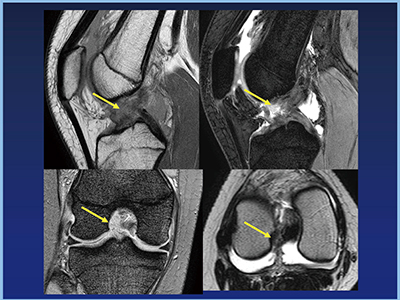

ACL完全断裂(図1)では,ACL中央部での断裂や大腿骨付着部での断裂が見られる。矢状断像だけでは診断が難しい場合もあるため,冠状断像や横断像で確認する必要がある。部分断裂も冠状断像や横断像で靭帯内部に高信号が確認できれば診断可能である。また,外側関節包靭帯またはanterolateral ligamentに強い牽引力が加わって生じるSegond骨折では,高確率でACLが断裂している。

図1 ACL完全断裂(ACL中央部での断裂)